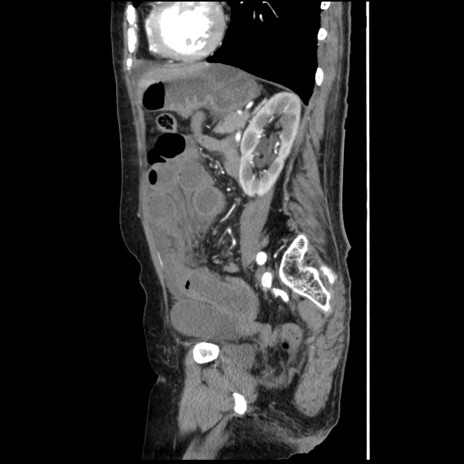

症例1(矢状断像)

【症例】80歳代女性

【主訴】腹痛

【現病歴】8時間前から腹痛あり来院。

【既往歴】糖尿病、脂質異常症、子宮体癌にて子宮全摘術

【身体所見】意識清明・会話良好だが腹痛で苦悶様、全腹部にわたって反跳痛と圧痛あり

【データ】WBC 13600、CRP 0.14、LDH 224、CK 90